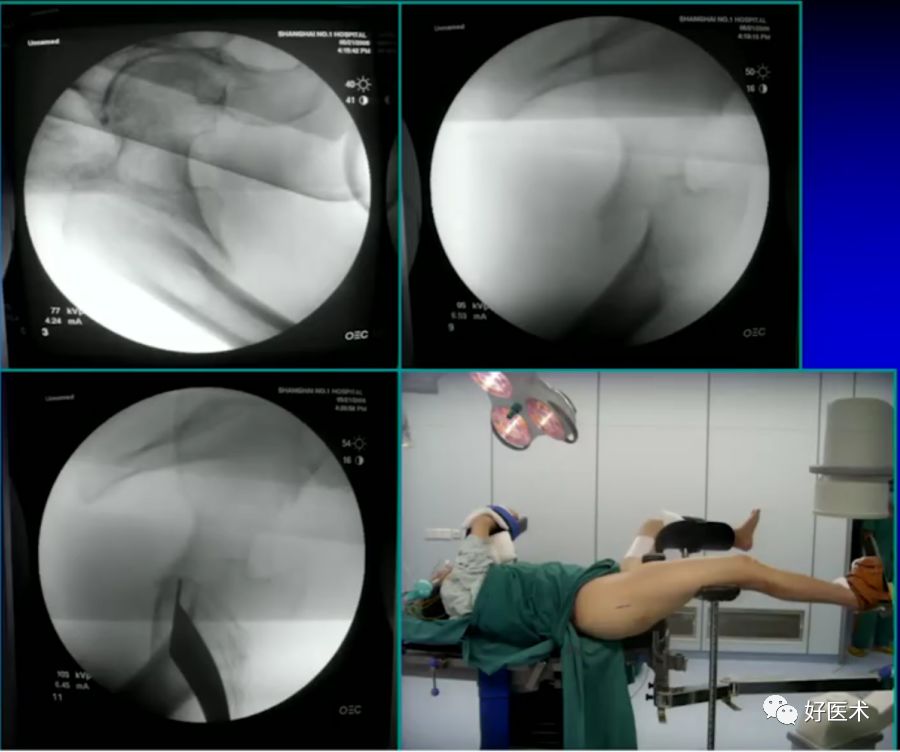

(四)介绍几种复位方法

1.撬拨技术

用克氏针或斯氏针对移位的骨折块进行撬拨复位。

病例一:女 94岁

体表定位与撬棒置顶

撬棒置顶后内收情况

正位进针位置调整情况

主钉插入后的导针正侧位

病例二:女 75岁

术前复位:

定位:

术后:

2.顶棒技术

用钉棒顶压移位骨折块来帮助复位。

病例三:女 82岁

四部分骨折,髓内钉,钢板

6.正确的股骨颈正侧位

侧卧位如何透股骨颈的侧位:

-

标准侧位

球管20-30°

侧卧位行转子间骨折固定

病例:男,34岁,高处坠落伤,仅骨折余正常

处理方法:

髓内钉(开放VS闭合)

钢板

其他

术前牵引

开口、定位

术中过程